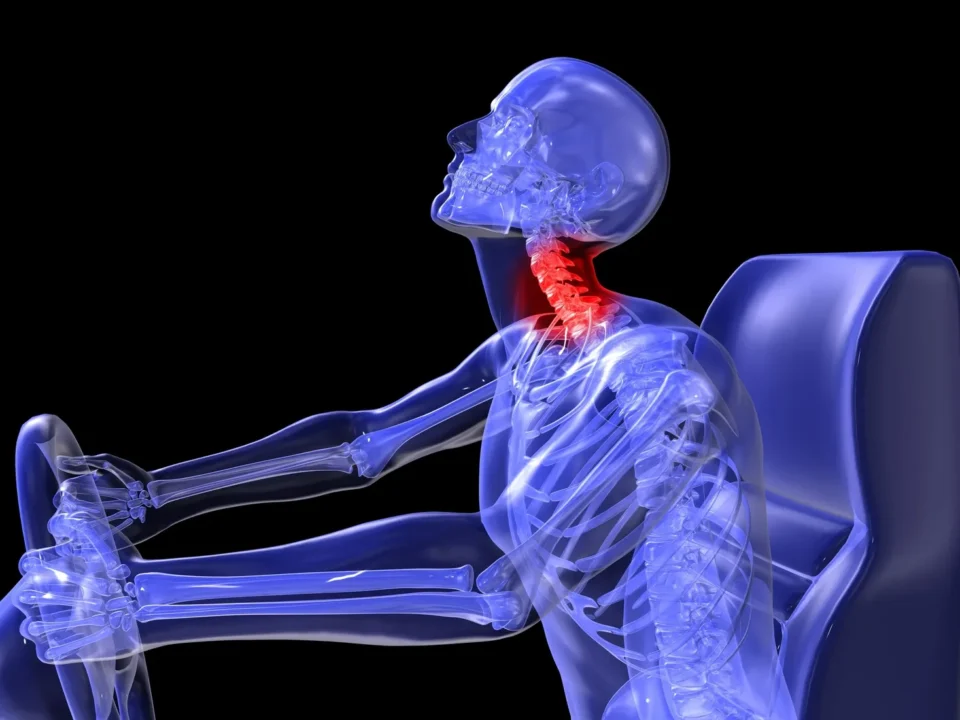

آسیبهای ستون فقرات :

تروما ناشی از تصادفات رانندگی یا سایر آسیبها میتواند باعث شکستگی یا جابجایی مهرهها شود و منجر به باریک شدن کانال نخاعی گردد.